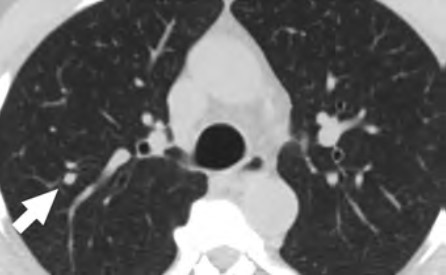

At the individual level, some of the barriers include decreased opportunities to provide accurate smoking history in the EMR, cost concerns related to insurance coverage of LCS and subsequent followups (Fig. 3), challenges to understanding LCS results when examinations show abnormal findings, fragmentation of care for management of abnormal LCS results and incidental findings, and difficulties navigating the complexities of health care systems [4, 8, 10]. Cost transparency and cost concerns are areas of active research, because cost influences how patients access and use health services [2]. For example, a recently published study evaluated the out-of-pocket cost of invasive procedures after LCS and showed that the rates of invasive procedures in commercially insured populations exceed those of invasive procedures in clinical trial participants [2].